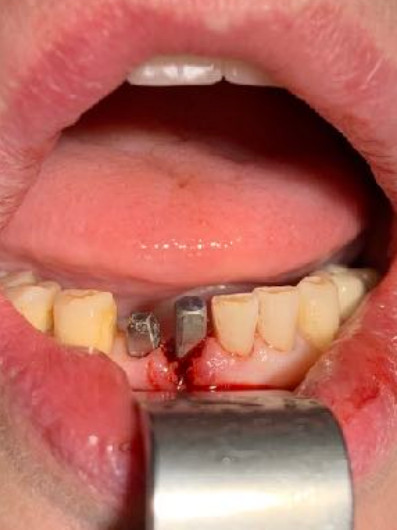

N.impianti inseriti

1

Zona dentale

41

Situaz.estrattiva

postestrattivo immediato

Carico occlusale

Immediato in leggera occlusione

Complicanze

nessuna